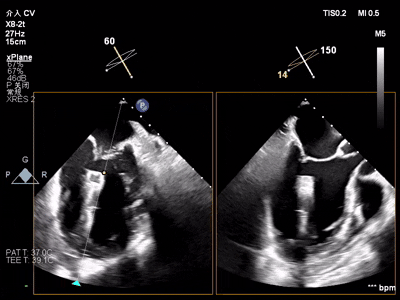

【术中操作(含关键步骤超声)】

鉴于患者术前心功能差、多支架植入的特殊情况,手术全程需兼顾“精准操作”与“保护心功能”双重要求:在全麻与经食道超声的协同引导下,团队先突破心功能受损导致的术野稳定性难题,稳步经心尖建立手术轨道与输送鞘;随后聚焦二尖瓣2偏3区精准置入一枚Ⅱf型夹合器,成功攻占这一解剖位置深、毗邻结构敏感、容错率极低而操作难度陡增的区域。